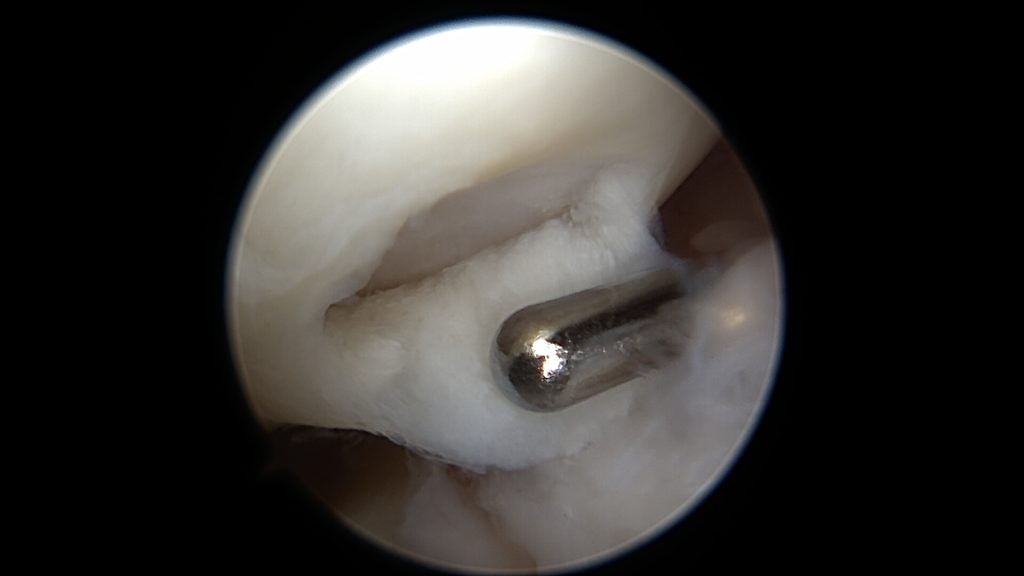

Powierzchnie uszkodzenia trzeciego stopnia wyrównuje się mechanicznie, aby rozpulchnione fragmenty chrząstki nie stanowiły powierzchni ciernej.